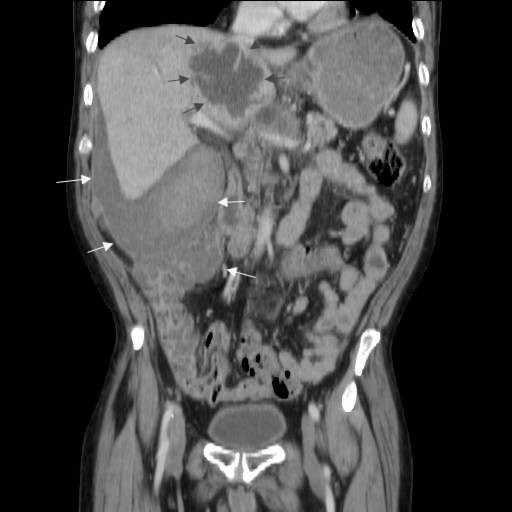

A 57-year-old man with a one year history of alcohol-induced chronic pancreatitis presented with a 1-month history of intermittent epigastric pain. He denied any associated nausea, vomiting, diarrhea, weight loss or other gastrointestinal symptoms. His past medical history was significant for hypertension, type 2 diabetes mellitus, dyslipidemia and chronic obstructive pulmonary disease. The abdomen was soft and non-tender. The liver and spleen were not felt, and no abdominal mass was appreciated. His physical examination was otherwise unremarkable. Laboratory evaluation revealed serum amylase of 356 U/L (reference range: 30-111 U/L) and a lipase of 679 U/L (reference range: 46-218 U/L). Complete blood counts, liver chemistries, carbohydrate antigen 19-9, and alpha-feto protein levels were all normal. Pancreas protocol CT scan of the abdomen revealed a 8x5 cm cystic fluid collection in the left liver lobe, an L-shaped subcapsular fluid collection inferior to right hepatic lobe 10x9 cm in size and a 2.4 cm complex fluid accumulation that involved the head and the superior aspect of the body of pancreas (Figure 1). CT guided diagnostic aspiration of the hepatic cystic lesion drained 100 mL of straw-colored fluid which showed no organisms on gram stain and was sterile on bacterial and fungal cultures. Cytological examination of the fluid did not reveal any malignant cells. The amylase level in this fluid was greater than 51,065 U/L which confirmed the diagnosis of intrahepatic pancreatic pseudocyst extension. At the time of CT guided aspiration, the pseudocyst was treated with percutaneous drainage with the placement of an 8F pig-tail catheter. The intrahepatic pancreatic pseudocyst extension failed to resolve even after 4 weeks of the pig-tail catheter placement (Figure 2). At this point, an ERCP was performed which revealed a normal cholangiogram. Pancreatography revealed a normal-appearing main pancreatic duct to the region of the pancreatic neck, and a ductal stenosis 12 mm in length was identified beginning at the pancreatic body near the neck. The main pancreatic duct and pancreatic duct branches were dilated upstream of the stenosis to about 7 mm (Figure 3). After performing an 8 mm ventral pancreatic sphincterotomy; the stricture was dilated with a 6 mm biliary dilating balloon and a 7F, 10 cm long pancreatic stent was inserted to the tail (Figure 4). Brush cytology and intraductal biopsy specimens were obtained from the stricture and revealed fibrosis and changes of chronic pancreatitis; they were negative for malignancy. EUS examination revealed a pancreatic head cystic lesion extending into the left hepatic lobe (Figure 5ab); fluid examination revealed an amylase of 54,450 U/L and the cytology was negative for malignancy. A follow-up pancreas protocol CT of the abdomen 6 weeks later revealed complete resolution of the pancreatic head fluid accumulation and the intrahepatic pancreatic pseudocyst and decrease in size of the L-shaped subcapsular fluid collection to 2x4 cm (Figure 6). Percutaneous drainage of the remaining L-shaped subcapsular fluid collection was discussed with the patient but he refused any percutaneous or surgical drainage. A follow-up pancreatogram revealed marked improvement in the pancreatic duct stricture. He remains asymptomatic after 9 months of follow-up.

Figure 1. CT scan of abdomen showing the intrahepatic pseudocyst in the left liver lobe along with an L-shaped subcapsular fluid collection inferior to the right hepatic lobe. |